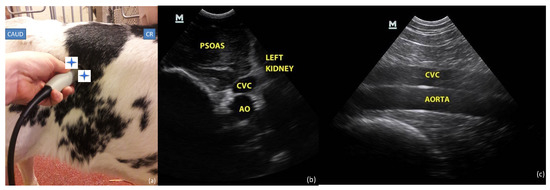

2.3.2. Paralumbar Window

2.4.2. Paralumbar Transversal and Longitudinal View